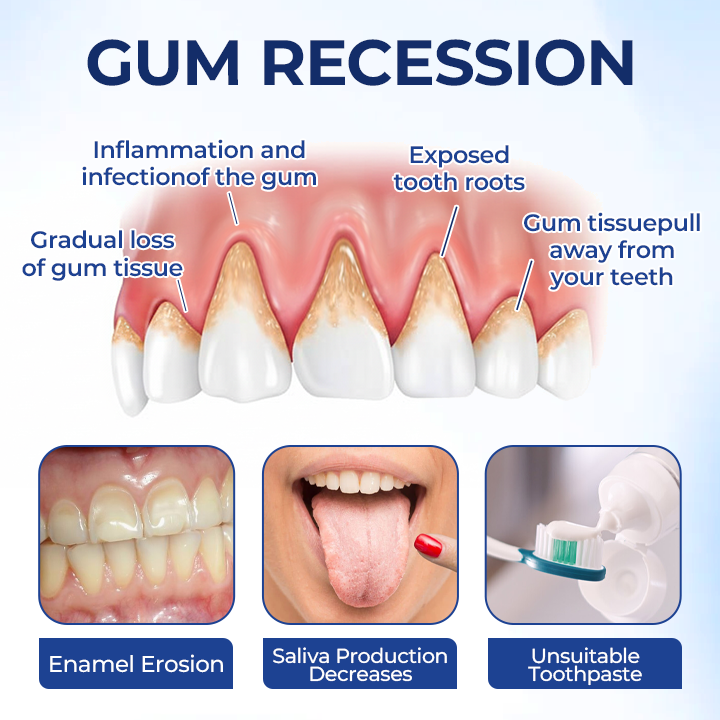

Periodontitis & Gum Recession — What’s Really Happening?

Periodontitis is a progressive gum disease caused by bacteria and inflammation.

As we age—especially after 30—our enamel thins, saliva decreases, and gums become more vulnerable to erosion, sensitivity, and recession. Poor oral habits or the long-term use of harsh toothpastes can further irritate gums and accelerate periodontal damage.